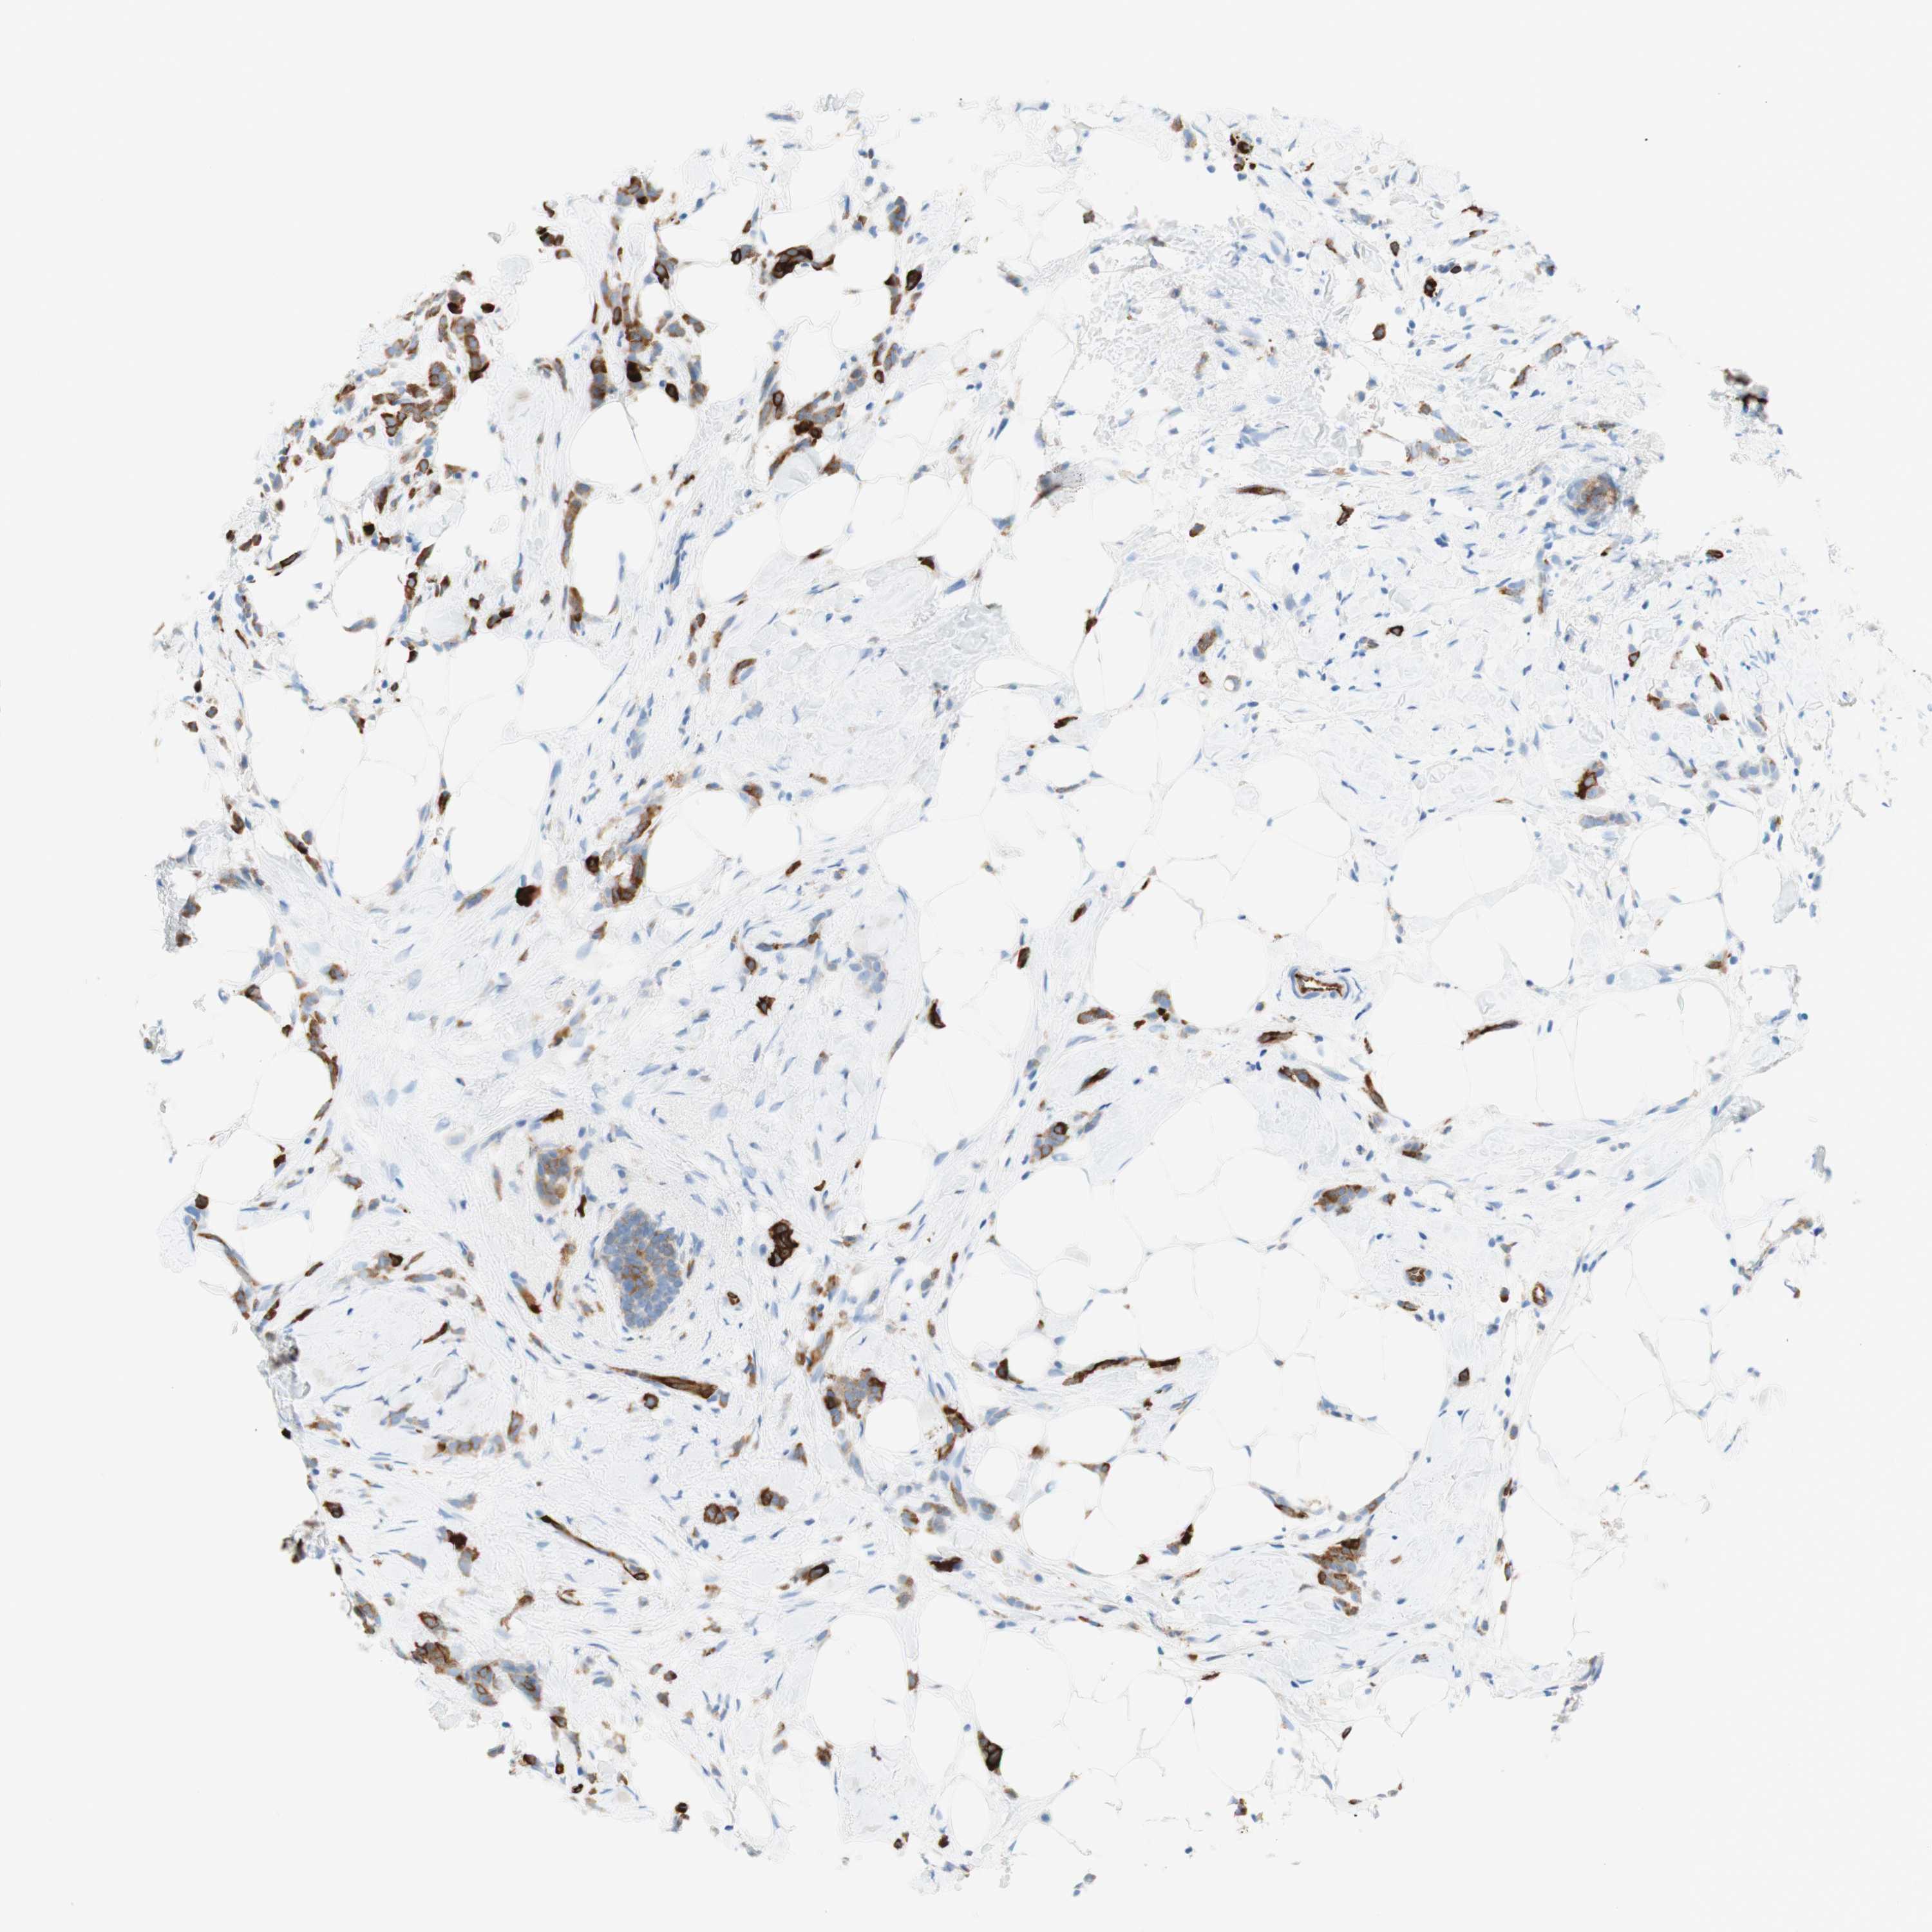

CANCER BREAST CANCER Show tissue menu

BRCA TCGA BRCA VALIDATION PROTEIN EXPRESSION